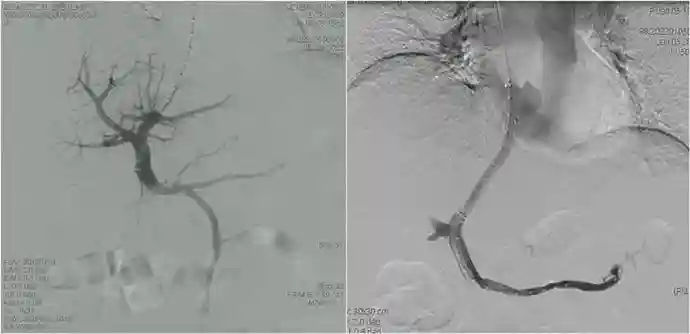

术前CT显示肝静脉闭塞,大量腹水

术中植入VIATORR支架,建立下腔静脉与门静脉分流道